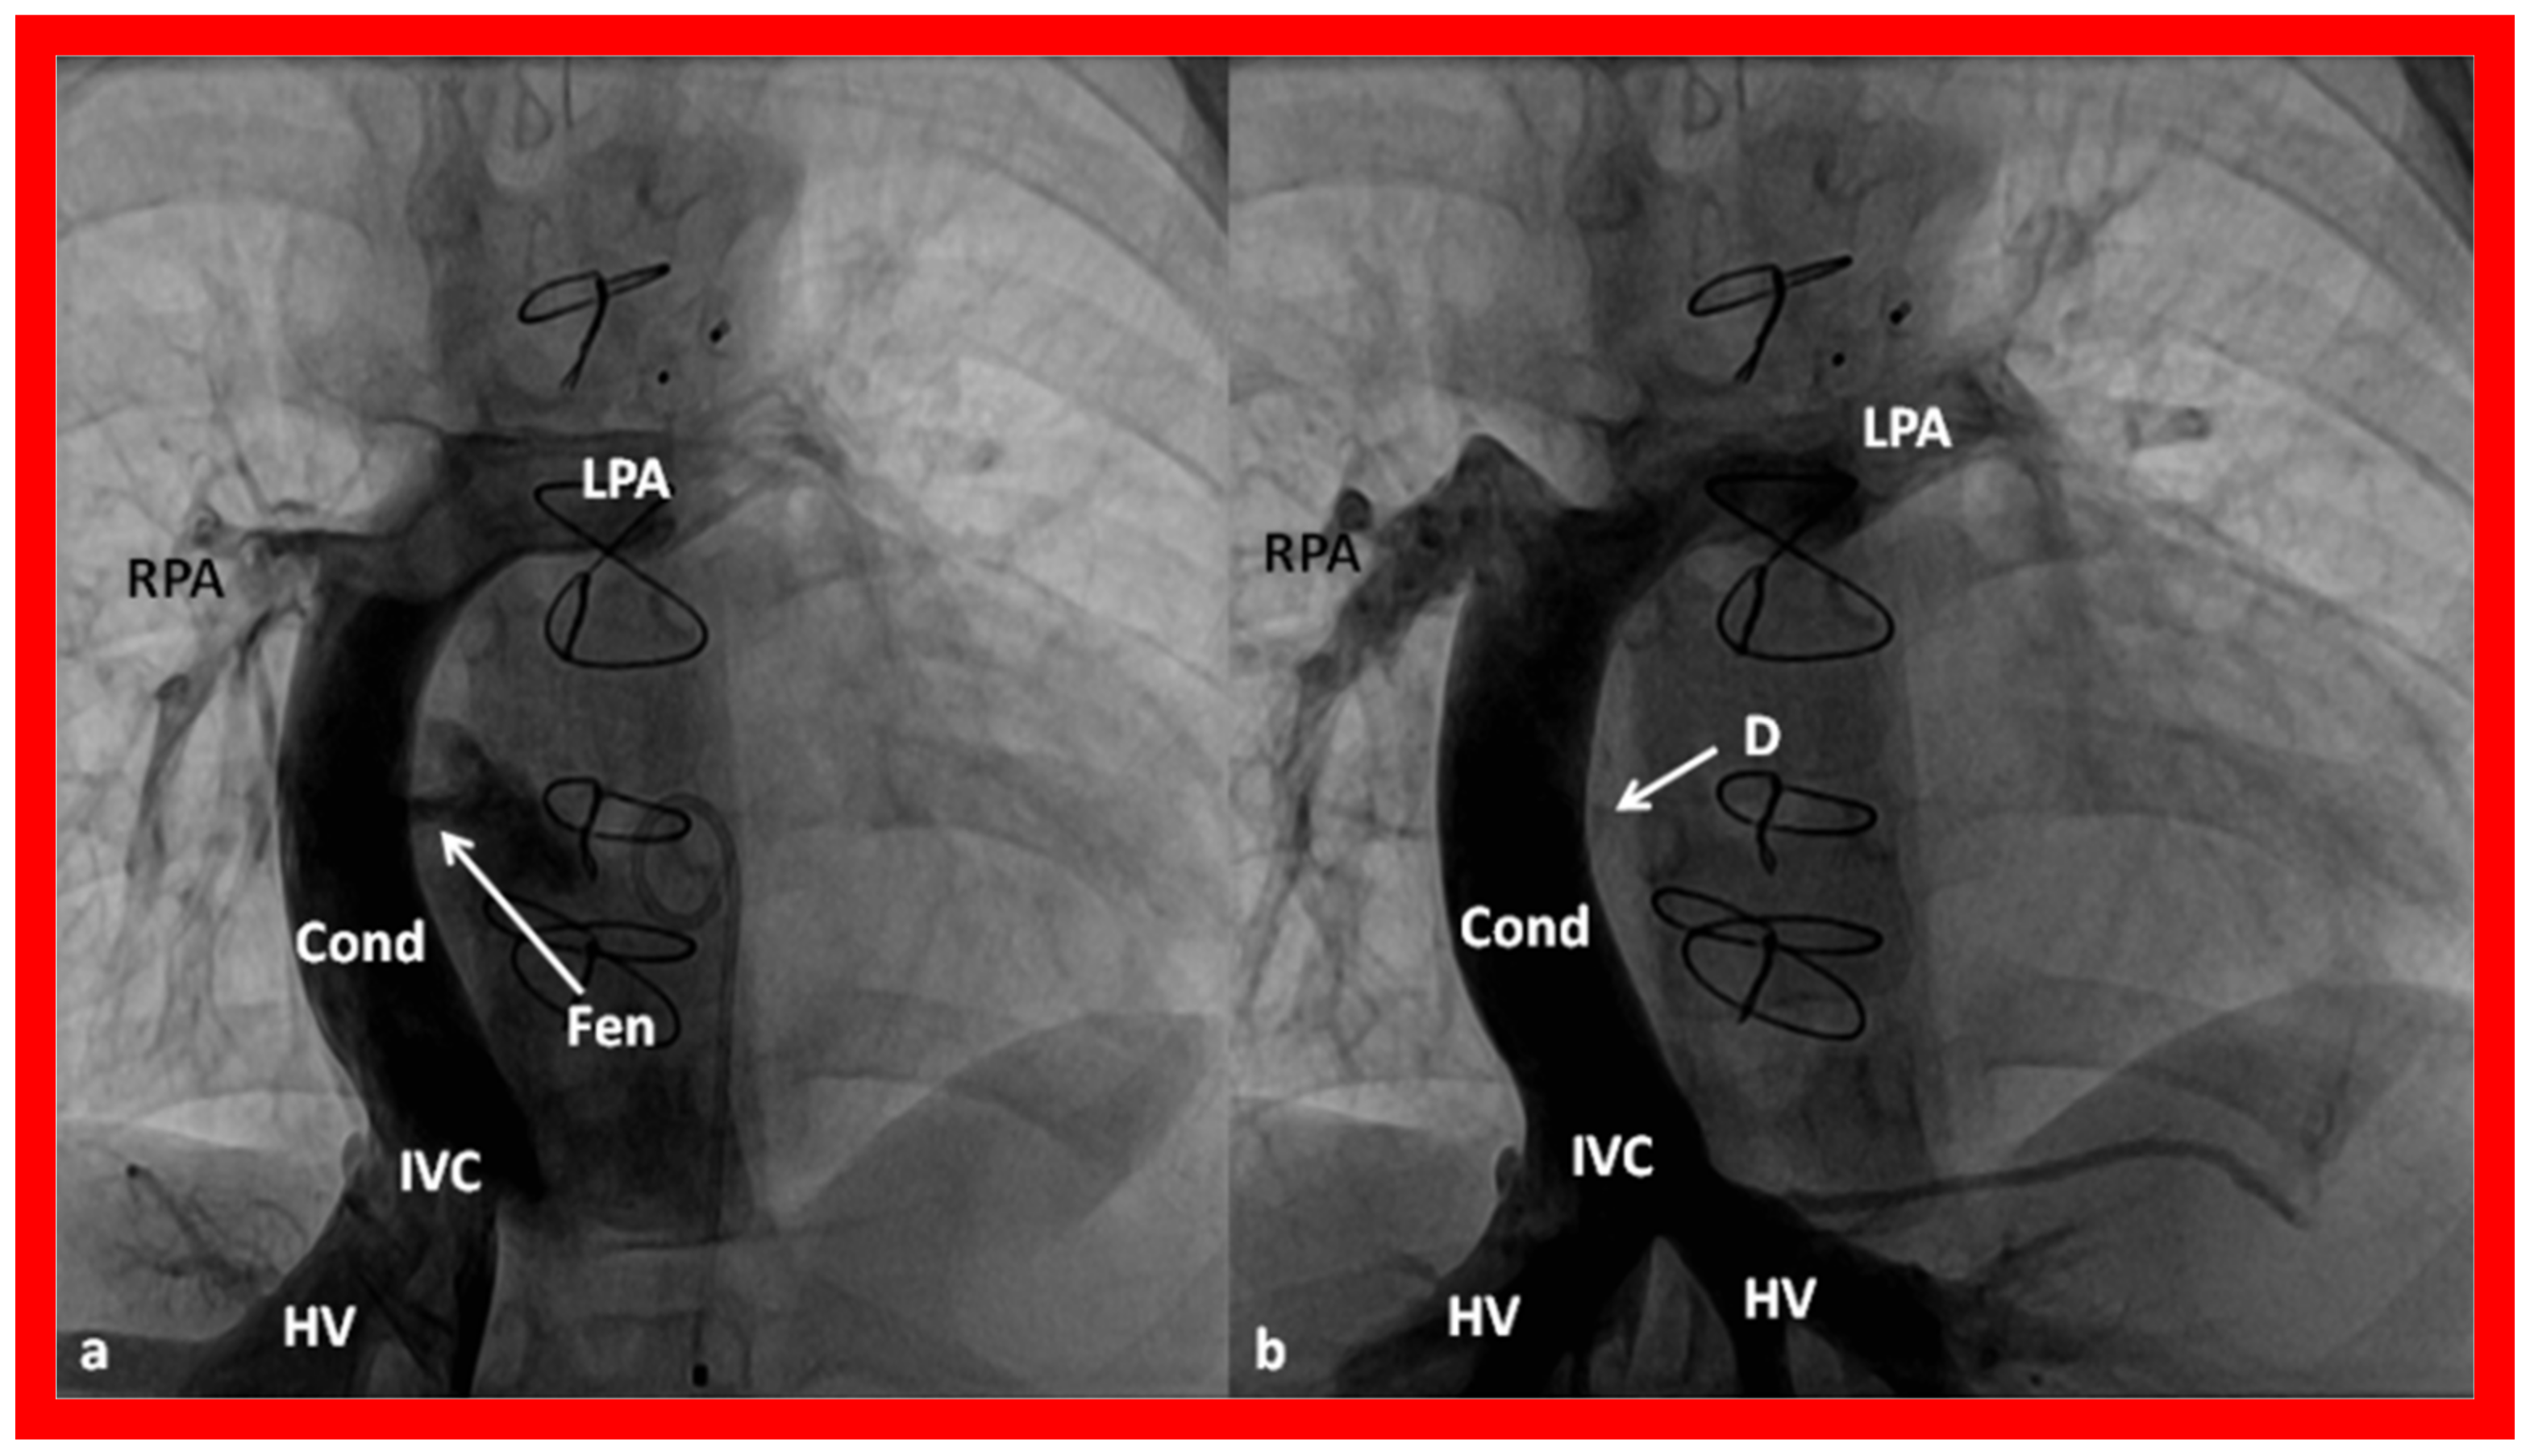

10.4.1. Stage IIIA

10.4.2. Stage IIIB